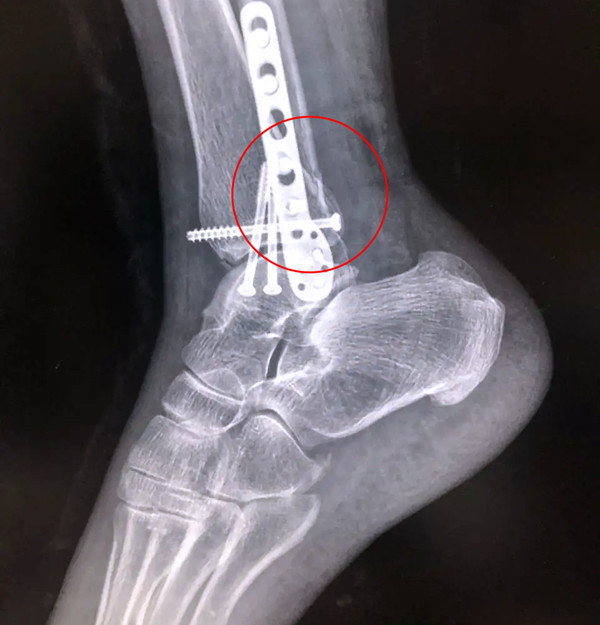

踝關節(jié)骨折在X影像上的表現(xiàn)有很多種。如內(nèi)踝骨折和外踝骨折,我們可以在影像上看到骨折處的骨折線是不連續(xù)的。還有后踝的骨折,內(nèi)踝、外踝、后踝聯(lián)合在一起發(fā)生的骨折,我們稱之為“三踝骨折”,這些都是在X影像上能夠顯示出來的。

后踝骨折

三踝骨折